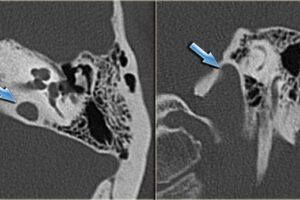

Temporal Kemik BT

Temporal Kemik BT nedir ?  Temporal Kemik BT, iç kulağı koruyan başın yan tarafında bulunan kemik yapıların kontrastsız bir çalışmasıdır. Ayrıca bölgeyi çevreleyen dokuya ve iç kulak yapısına da …